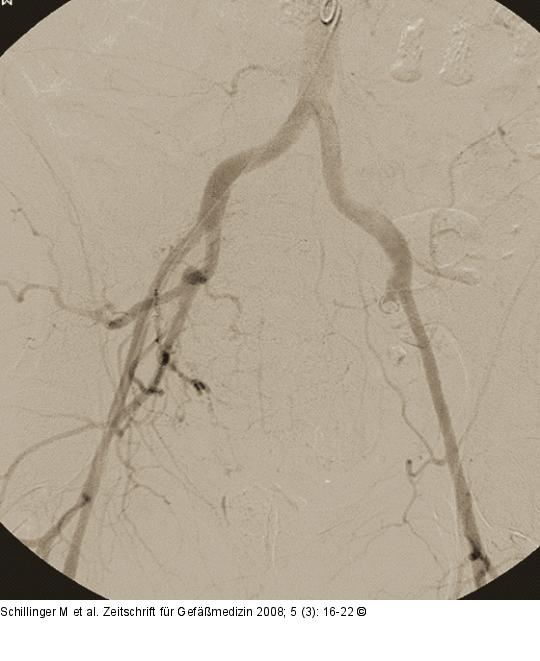

Abbildung 1: Morbus embolicus Übersichtsangiogramm der Beckenetage. |